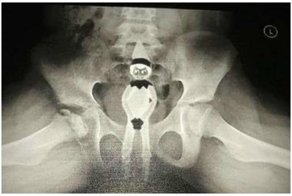

Кто крайний на фиброэзфст... скопию?

Фибро - волокно, эзофаго - пищевод, гастро - желудок, дуодено - Двенадцатиперстная кишка, скопия - смотреть. Получается: засунем волокно в пищевод затем в желудок затем в 12 перстную кишку, чтобы посмотреть. В медицине много латыни, так же как ЛОР - Л - Ларинг - горло, О - ото - ухо, Р - рино - нос. Забавно что врач Оториноларинголог = ЛОР, а по факту ЛарингоОтоРинолог, если использовать привычное сокращение (ЛОР), а привычное ухо горло нос - отоларингоринолог. Вот такие пироги.